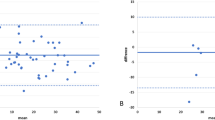

In sagittal plane, a proportional error was observed between the 2D and 3D TK and LL measurements (Fig. 5a, b) while an agreement between the 3D PP and 3D RP measurements for TK and LL measurement was shown (Fig. 5c, d). In terms of LL measurements a large bias (10°) was observed between the 2D and 3D measurements (Fig. 5b). In the frontal plane, 2D and 3D measurement showed agreement for TC and LC measurements (Fig. 6a, b).

a Bland–Altman plots of TK measurements showing an increased bias between the 2D and 3D PP measurements as the average TK increased (Bias = −4.3°, and 95 % limits of agreement 11.3 to −19.1). A negative value shows a higher 3D PP TK value. b Bland–Altman plots of TK measurements showing an agreement between the 3D RP and 3D PP measurements (Bias = 2.9°, and 95 % limits of agreement 11.2 to −5.8). A negative value shows a higher 3D RP TK value. c Bland–Altman plots of LL measurements showing an increased bias between the 2D and 3D PP measurements as the average LL increased (Bias = −11.4°, and 95 % limits of agreement 6.8 to −29.1). A negative value shows a higher 3D PP LL value. d Bland–Altman plots of LL measurements showing an agreement between the 3D RP and 3D PP measurements (Bias = 1.9°, and 95 % limits of agreement 5.9 to −1.9). A negative value shows a higher 3D RP LL value